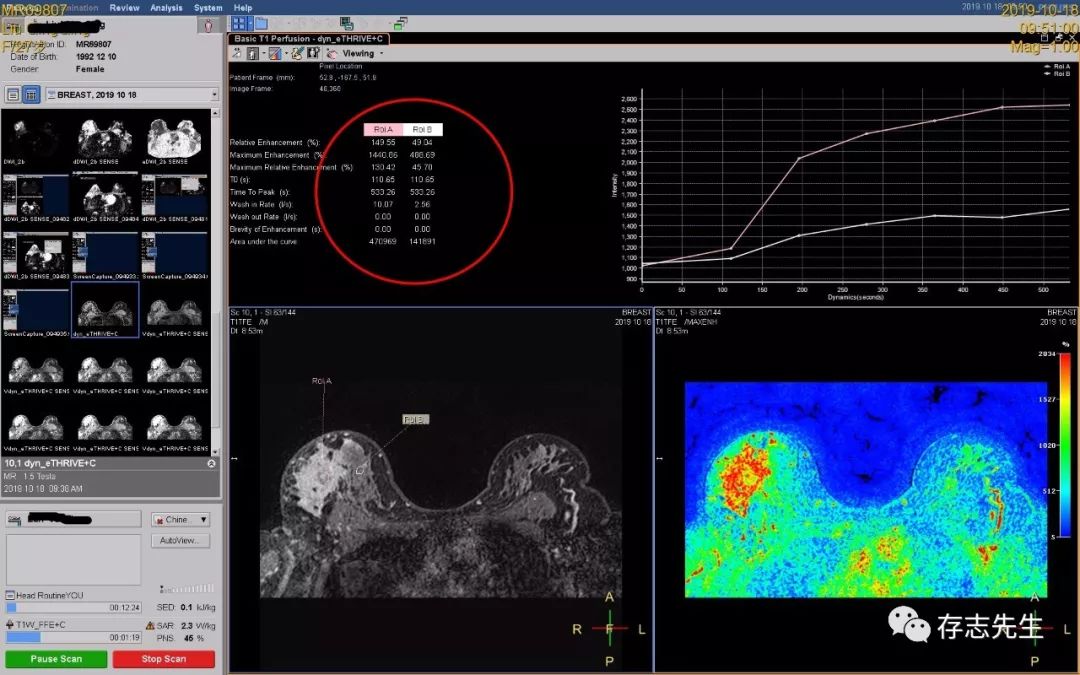

5、T1灌注+动态增强曲线,原始图像上选择T1灌注软件;

在工具栏中选择画ROI,在感兴趣区选取合适的ROI做动态增强曲线;

保存结果:在工具栏中选择Viewing菜单下Capture,截图保存,同时在工具栏中选择Generate,生成灌注彩图。这样不仅能获得动态增强曲线,同时能获得灌注分析信息等多种有价值的参数图和灌注数据,辅助诊断。